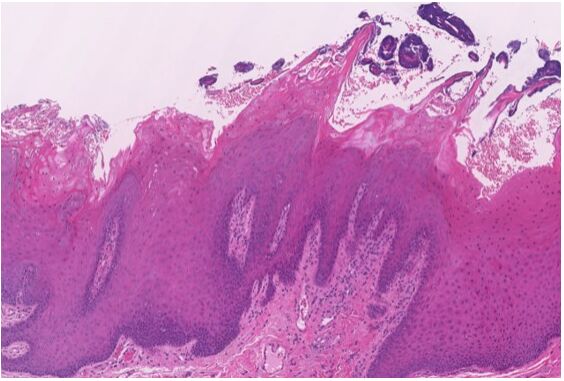

7.關於咀嚼性黏膜(masticatory mucosa)的敘述,下列何者錯誤?(A)硬腭黏膜為咀嚼性黏膜 (B)牙齦為咀嚼性黏膜 (C)黏膜性質為角化(keratinized)或不完全角化(parakeratinized) (D)頰黏膜為咀嚼性黏膜